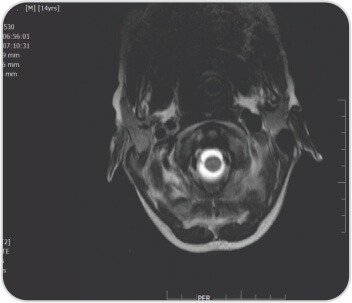

মস্তিষ্কের সাথে পুরো মেরুদণ্ডের এমআরআই দীর্ঘ সেগমেন্টের পূর্ববর্তী এপিডুরাল সংগ্রহ প্রকাশ করেছে যা T2-তে হাইপারিনটেন্স এবং T1-এ হাইপোইনটেন্স ছিল যার লেয়ারিং C2 থেকে D8 স্তর পর্যন্ত প্রসারিত হয়েছে যার ফলে সার্ভিকাল এবং ডোরসাল কর্ডের পশ্চাৎ স্থানচ্যুতি এবং কম্প্রেশন-সম্ভাব্য রক্তক্ষরণ, পোস্টেরিয়র প্যারাস্পাইনাল নরমের মৃদু মচন। সার্ভিকাল অঞ্চলে টিস্যু লক্ষ্য করা গেছে। ল্যাবরেটরি তদন্তে Hb7.5gr%, TLC11, 700/mm3, প্লেটলেট 2.92lakhs/mm3, Rbs 96 mg/dl, সিরাম ক্রিয়েটিনিন 0.5mg%, Bl.urea 37.0 mg%, Serum Na+ 128, S.K, S.3.6+93.0। Cl- 21.90 meq/l মোট বিলিরুবিন 13.70 মিলিগ্রাম% (সরাসরি 8.20 পরোক্ষ 254) SGPT 180u/l SGOT 265.00 u/l Alk ফসফেটেস 6.00, মোট প্রোটিন 2.80 g% (Alb.3.20b.68.0%), 8.0b%। PT 86.8 সেকেন্ড INR > 2.62, APTT 7 সেকেন্ড। HAV IgM অ্যান্টিবডি পজিটিভ: 3; HBsAg, HBeAg, HCV, HIV: প্রতিক্রিয়াশীল নয়; ANA প্রোফাইল নেতিবাচক ছিল। তাকে নিবিড় পরিচর্যা ইউনিটে ভর্তি করা হয়েছিল এবং প্যারেন্টেরাল ভিটামিন কে ইনজেকশন এবং ভেন্টিলেটরি সাপোর্টিভ কেয়ার সহ 3 ইউনিট এফএফপি, 6টি পিআরবিসি পেয়েছিলেন। নিউরো সার্জারির পরামর্শের পরে C2-C5 ল্যামিনোপ্লাস্টি এবং ভর্তির 15 দিনে হেমাটোমা সরিয়ে নেওয়া হয়। 2 তম দিনে, ট্র্যাকিওস্টোমি করা হয়েছিল এবং ধীরে ধীরে ভেন্টিলেটর ছাড়ানো হয়েছিল। পুনর্বাসন কেন্দ্রে বিপ্যাপের সহায়তায় 2.90 তারিখে তাকে ছেড়ে দেওয়া হয়েছিল। কোয়াড্রিপ্লিজিয়া স্রাবের সময় উপরের অঙ্গে গ্রেড 157 শক্তি এবং মোট বিলিরুবিন 68 mg/dl, SGPT 2, SGOT XNUMXu/l সহ টিকে ছিল। দুই সপ্তাহের ফলো-আপে তিনি স্পাস্টিক কোয়াড্রিপ্লেজিয়া - সমস্ত অঙ্গে গ্রেড XNUMX শক্তি, স্থিতিশীল হেমোডায়নামিক্স এবং স্বাভাবিক লিভার ফাংশন পরীক্ষায় আরও উন্নতি করেছেন।